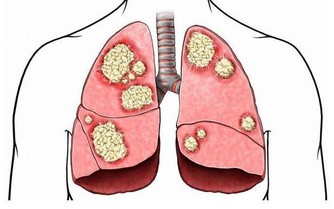

腦血栓,離我們遠嗎?

腦血栓不但影響患者身心健康嚴重的甚至導致癱瘓。

那麼,腦血栓的前兆都有哪些呢?

得了腦血栓又會有哪些癥狀呢?為家人,看一眼!腦血栓前兆